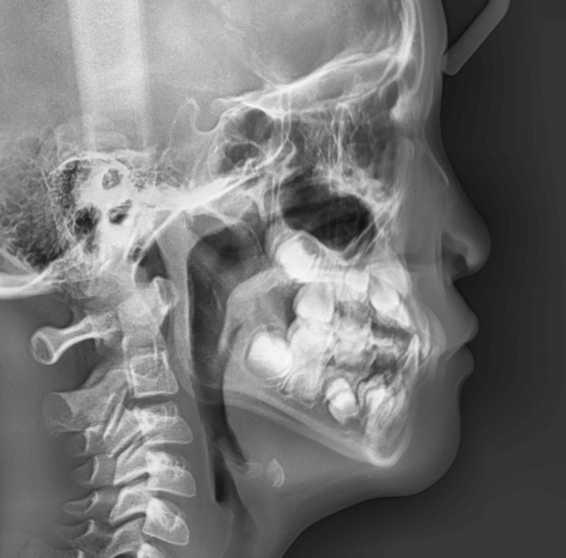

STEP2 精密検査

カウンセリング後、本格的に治療を進めるために精密検査に移ります。より詳しい口腔内の検査、顔・口内の写真撮影、レントゲンやCT撮影、歯型取りが具体的な内容です。顎の骨の歪みをはじめ、骨格的な問題が無いかも診察します。

早期矯正治療 反対咬合症例①

主訴 | 前歯がうまく噛み合わず、食事時に違和感があるとのことで来院されました。保護者様からは、将来的な歯並びの不安についてもご相談がありました。 |

診断結果 | 8歳7か月の男児 前歯の反対咬合(下顎前突)診断 |

治療内容 |

|

治療後の経過 | 動的治療は1年3か月で完了。反対咬合は改善されました。現在は3〜4か月ごとの定期検診で経過観察中で、今後本格的な矯正治療へ移行予定です。 |

治療期間 | 動的治療期間:1年3か月 治療回数:11回 |

治療費用 | 400,000円(税別) |